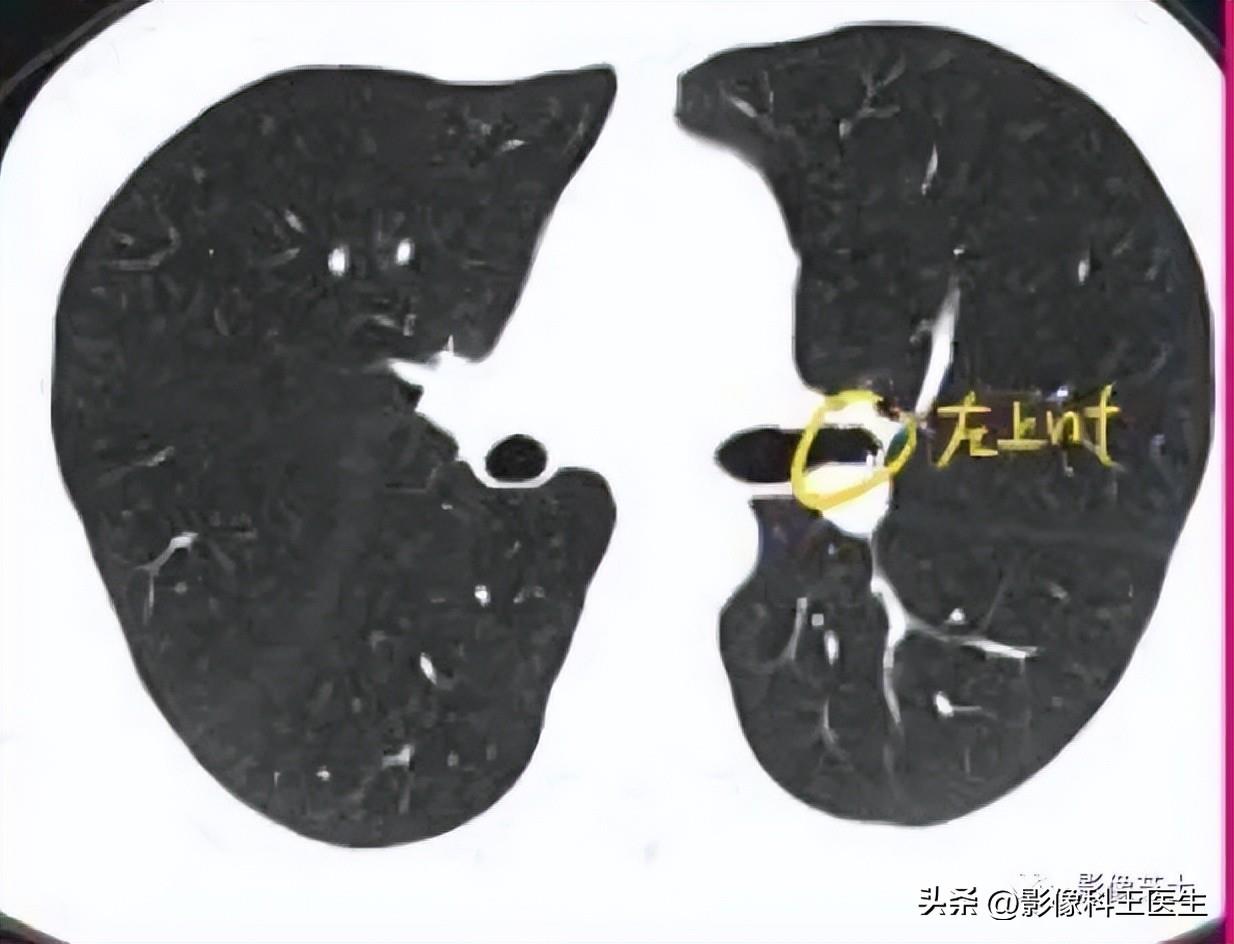

肺段、支气管分段CT解剖(详细标注)

肺部解剖分叶分段CT

肺的分段